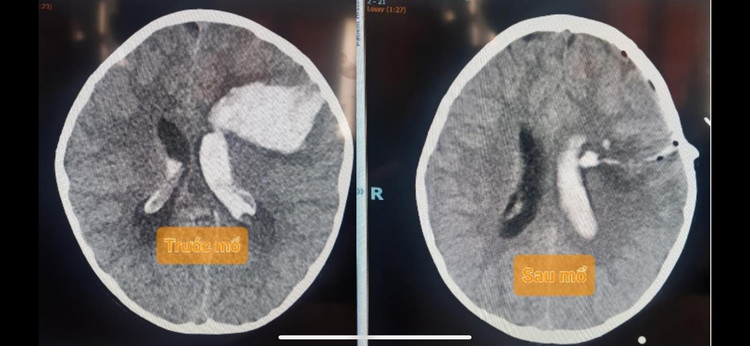

Cả 3 bé gái đều đột ngột hôn mê trước khi vào viện, 2 bé gái sinh năm 2013 N.T.H.Y và N.H.H.Y, 1 bé sinh năm 2017 T.N.N.H. Cả 3 cháu bé đều được chụp CT scan sọ có thuốc phát hiện có một búi dị dạng đường kính 2 X 3 cm ở thuỳ thái dương, thuỳ chẩm và thùy trán gây xuất huyết não – não thất.

3 bệnh nhi được tiến hành phẫu thuật mở sọ lấy máu tụ và bóc lấy toàn bộ búi dị dạng. Tình trạng sau mổ các cháu tỉnh táo, vết mổ lành tốt.

| Hình ảnh phim chụp não của bệnh nhi - ảnh BVCC |